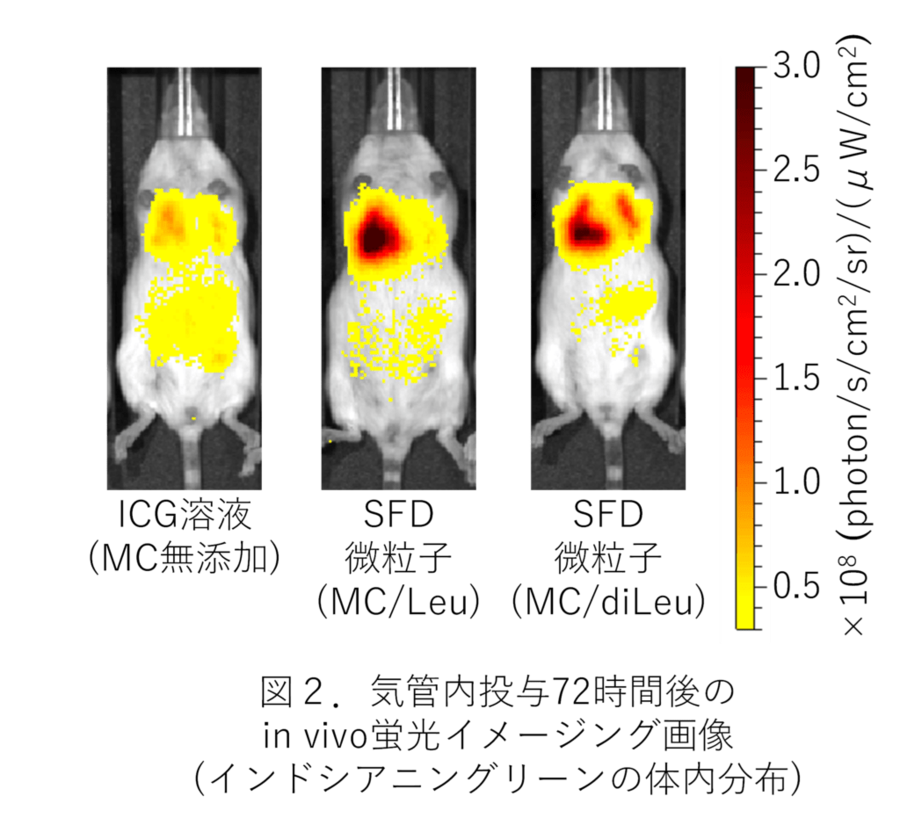

これらのSFD微粒子をマウスに気管内投与した後、モデル薬物として含有したインドシアニングリーン由来の近赤外蛍光をin vivo蛍光イメージング注3)により経時的に検出・解析した結果、MCを含む水溶液と同様にSFD微粒子でも、MCを含まないICG水溶液と比べて肺局所でより長時間にわたり強い蛍光が検出され、MC含有による肺内での薬物滞留性の向上効果が示唆されました (図2)。一方、肺障害性マーカーとして測定した体重・肺重量・動脈血酸素飽和度・気管支肺胞洗浄液注4)中の有核細胞数に変化はみられず、これらのSFD微粒子の高い安全性が窺えました。